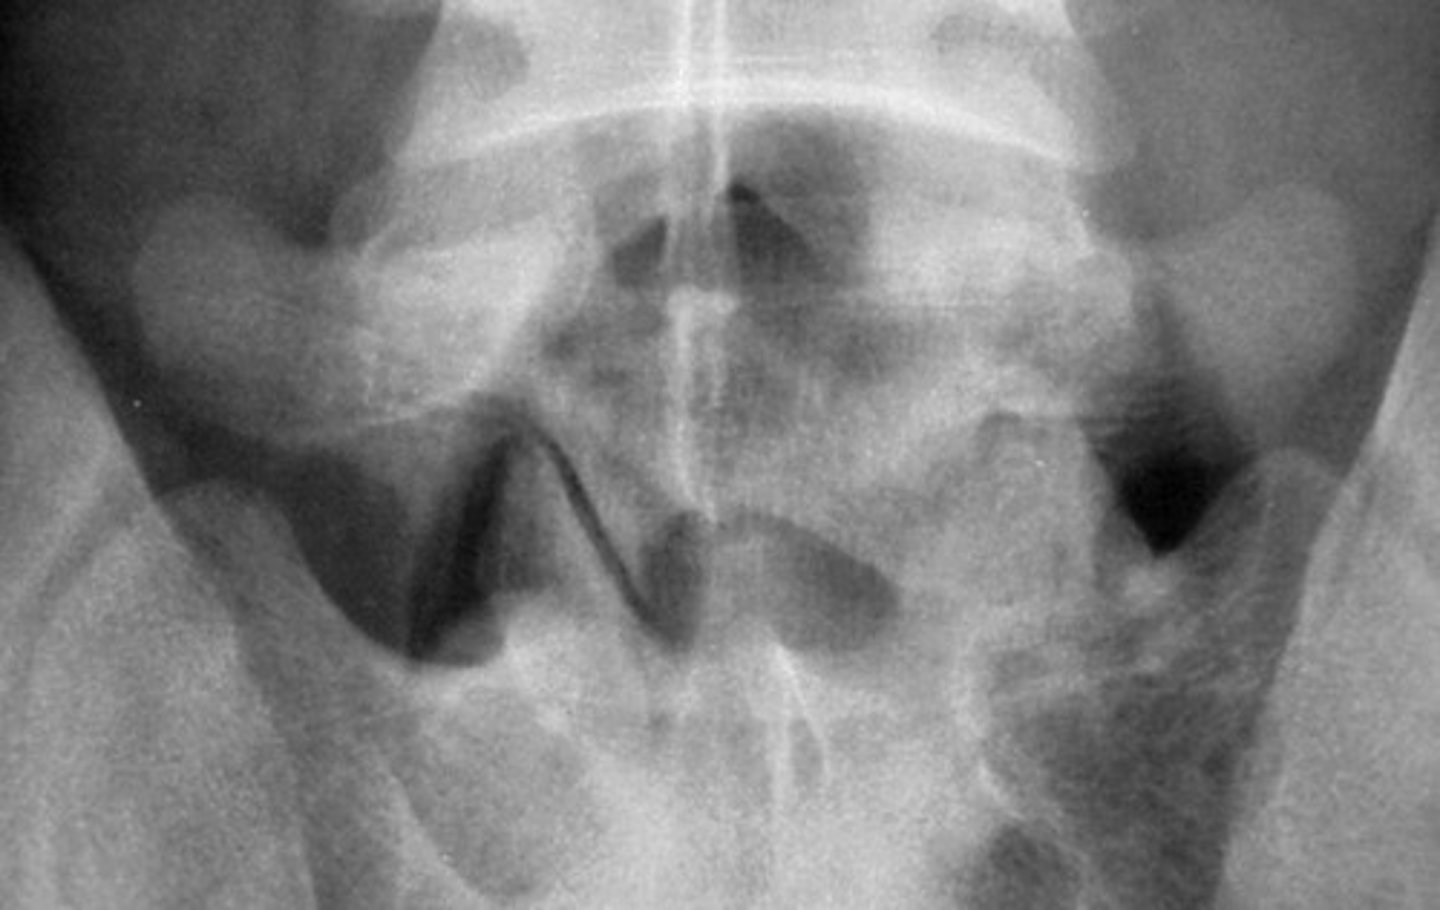

Facet Tropism

"Trop" = to turn

Asymmetric orientation of the facets = coronal AND sagittal facets at one level